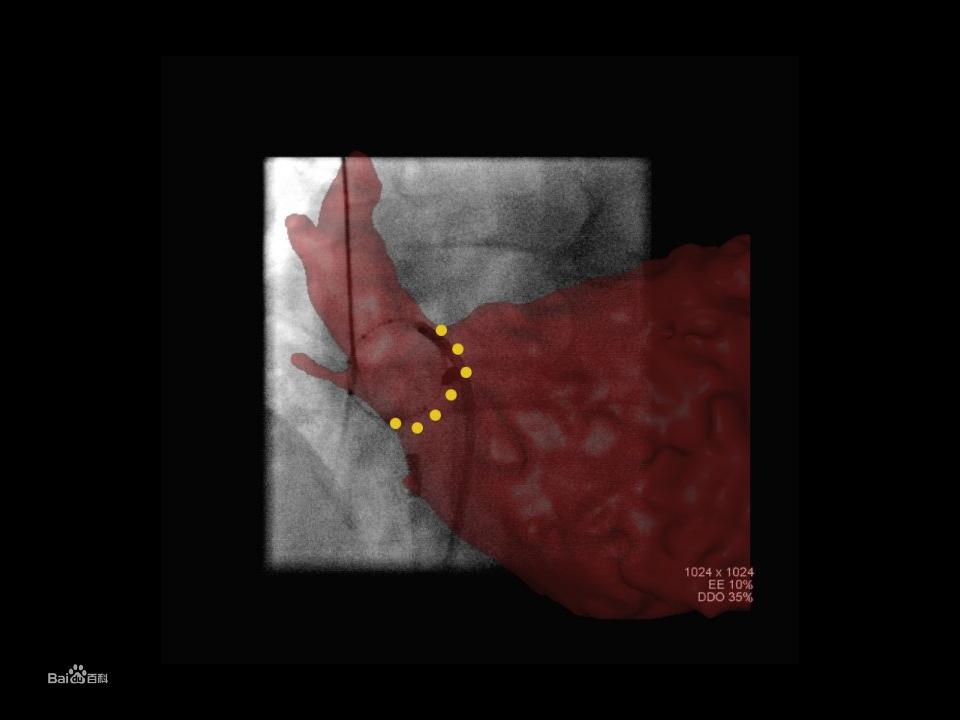

並且,腹主動脈瘤的腔內治療技術的發展,推動了血管造影系統在血管手術環境中的套用。 特別是對於複雜的血管腔內移植物,複合手術室應成為基本條件。同時,它也很適用於急診手術治療。 有些外科醫生不止認可外科手術進行時的血管腔內移植物,他們同時也使用血管造影系統和應用程式為手術做計畫與引導。由於患者在術前CT和術中透視的解剖位置改變,以及嵌入的堅硬材料而導致的改變,對術中更精準的規劃設計提出了相應要求,如果外科醫生在手術進行時運用鏇轉血管造影術,能對主動脈採用自動分割,對腎動脈和其他位置進行3D標記,然後覆蓋二維透視疊加,並且能隨著C型臂角度/位置或手術床的變化而進行更新。

將工作站的信息添加到透視圖像的另一種可供選擇的方法是疊加,可以在疊加三維圖像的透視圖像上對感興趣結構的部分進行手動或自動分割,勾畫標記輪廓。這為透視圖像提供了額外的信息。有些套用軟體可以自動標記,也可以讓醫生和技師手動添加標記點。舉個病例:了給一個腹主動脈瘤放置一個開窗的覆膜支架,在3D圖像上標記腎動脈開口,然後將標記的3D圖像疊加在實時透視圖像上。在3D標記完成後,它會與實時透視圖像自動匹配,讓醫生可以在實時透視圖像始終觀察到標記好的腎動脈開口,從而讓開窗支架準確定位。